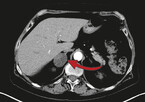

Drei Prozent der über 50-Jährigen haben Nebennierentumore. Bei den über 80-Jährigen ist sogar jeder zehnte betroffen. 80 bis 90 Prozent dieser Tumore, die meist zufällig, zum Beispiel bei einer Computertomographie bei Gallenproblemen, Nierensteinen oder Rückenleiden, entdeckt werden, sind jedoch gutartig und vermeintlich harmlos.

Doch eine leicht gesteigerte Produktion des Hormons Kortisol, die viele dieser Tumore mit sich bringen, spaltete vor einiger Zeit die Meinungen. Muss man den Tumor operativ entfernen oder nicht?